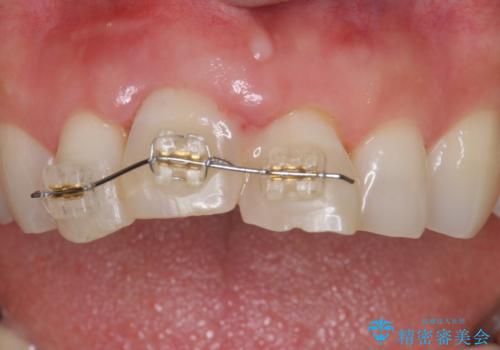

- 転んで前歯が折れたとのことで来院されました。

検査の結果、歯は大きく折れておらず、骨の中に埋め込まれていた状態であったため、部分矯正で歯を引っ張り出していきます。